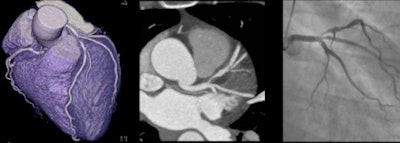

| A 48-year-old woman with a tight stenosis in the proximal left anterior descending coronary artery was a perfect candidate for stenting. A circumscribed lesion can be seen in the artery. Her heart rate was 58 beats per minute and she received 4 mSv of radiation. All images courtesy of Dr. Christoph Becker. |